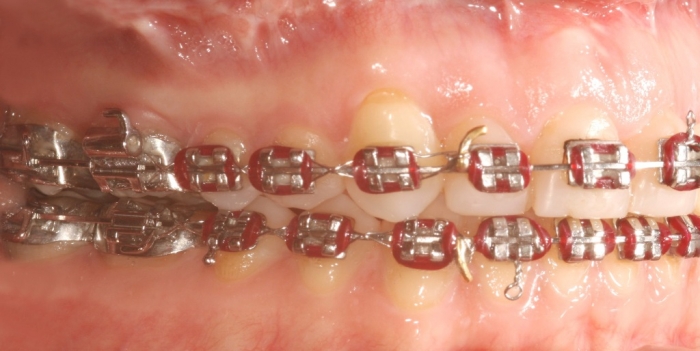

Imagem inicial - Clínica Cliniface

Imagem inicial